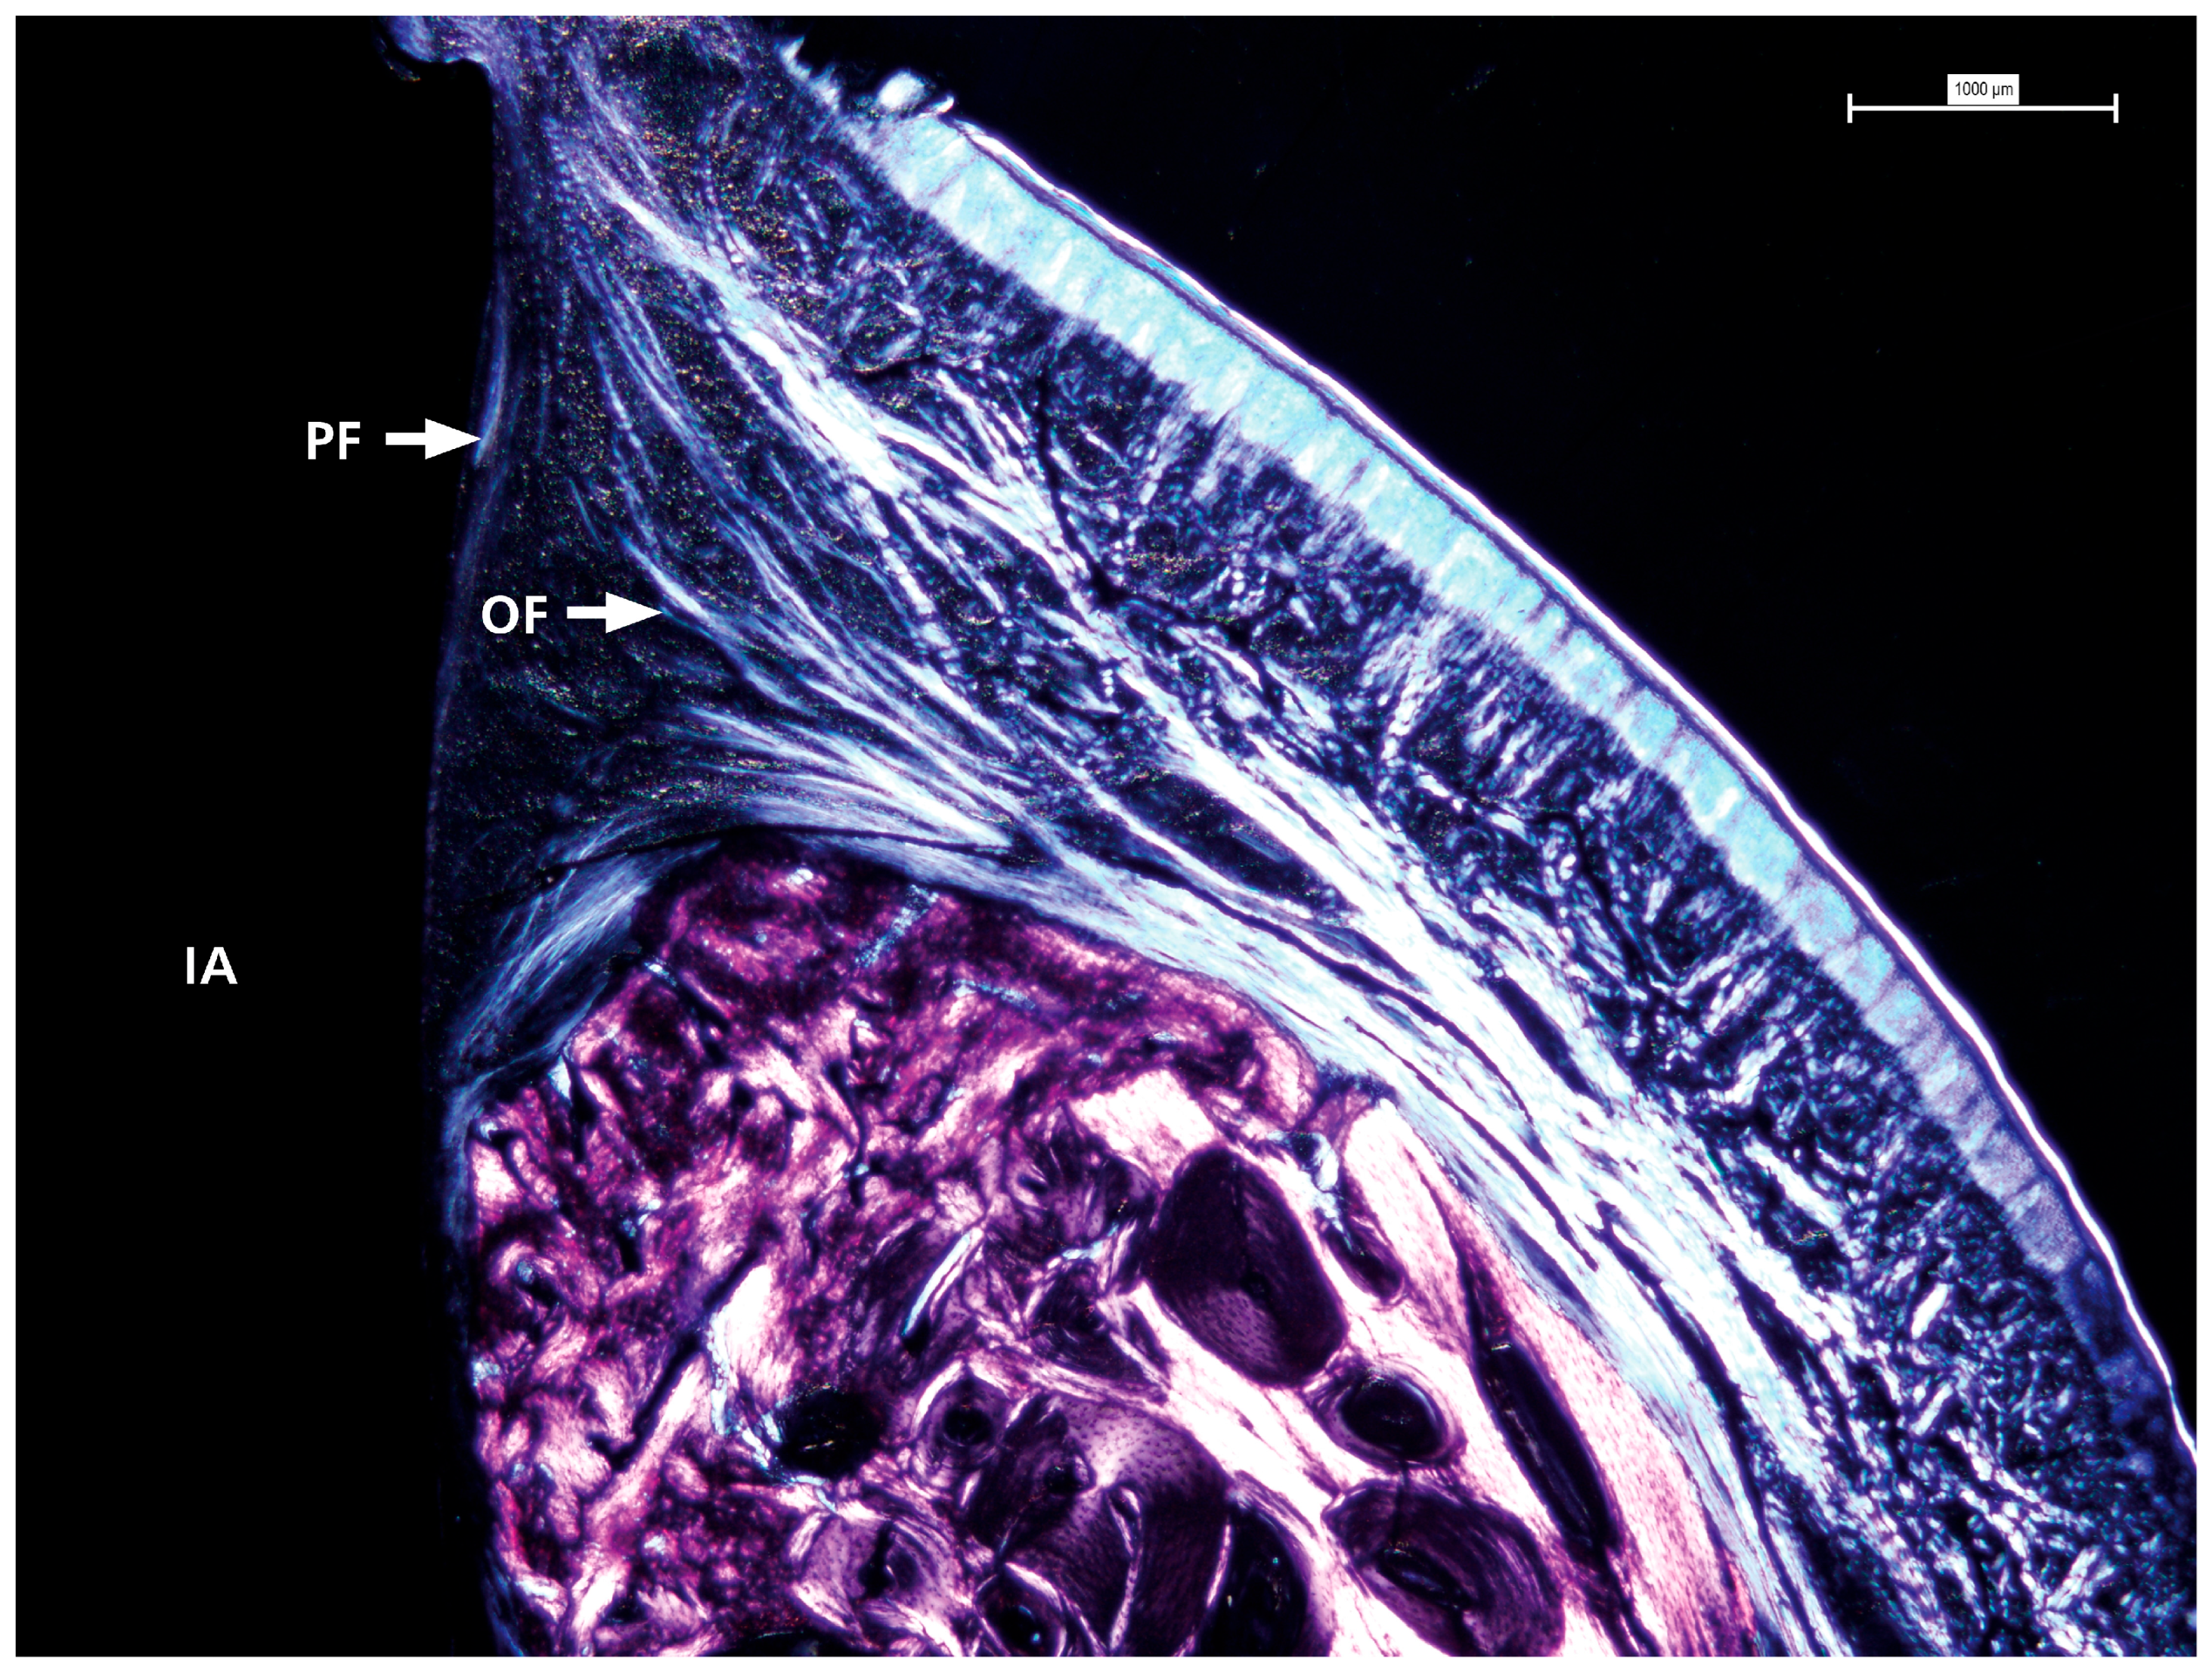

3.3. Polarized Light

Polarized light microscopy was used to examine the characteristics of the surrounding soft tissue (see Figure 5). This analysis consistently revealed a pattern across all samples in the distribution and orientation of collagen fibers around dental implant abutments. These fiber bundles were mainly associated with the abutment surface, with most samples showing complete bone coverage of the implant-abutment interface. The fibers originate from the nearby connective tissue, and their arrangement is more complex than a simple circular pattern. Instead, they are oriented obliquely and perpendicularly to the abutment surface, indicating a dynamic interaction between the abutment and soft tissue. This organization may influence the stability and adaptation of the soft tissue around the implant.

Figure 5.

The detailed view shows the presence and distribution of collagen fibers with visible oblique and perpendicular arrangements in contact with the prosthetic abutment. IA = implant abutment; PF = perpendicular fibers; OF = oblique fibers.

Polarized light microscopy revealed collagen fiber bundles arranged obliquely and perpendicularly at the abutment-tissue interface. This orientation is biologically significant because collagen fibers aligned transversely or obliquely can better resist compressive and tensile forces, thereby enhancing the biomechanical resilience of the peri-implant mucosa and contributing to soft tissue stability. These findings are consistent with prior investigations showing that collagen fiber orientation plays a key role in establishing a functional peri-implant barrier and in distributing mechanical loads [21,22]. Experimental models have further shown that immediately loaded implants can promote a higher proportion of transversely oriented collagen fibers, associated with improved mineralization and load adaptation of peri-implant bone [23]. More recent studies also emphasize that collagen organization around transmucosal abutments supports biological sealing and may protect against epithelial down-growth and microbial penetration [24]. Collectively, the collagen orientation observed in this study suggests that the hybrid conical implant design may foster favorable conditions for both biological integration and mechanical stability of peri-implant soft tissues.